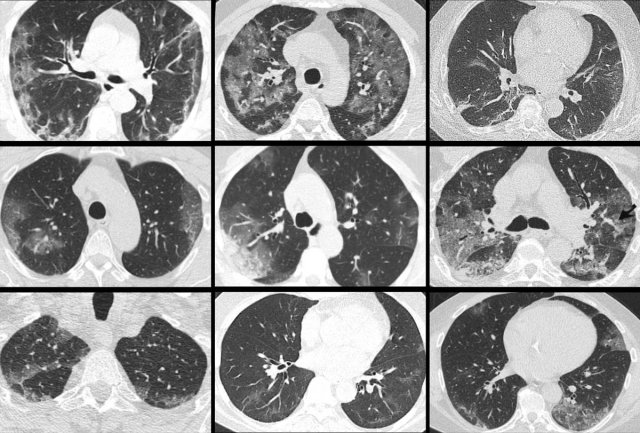

Viral pneumonias show overlapping features on CT.

Influenza virus infection can result in bilateral ground-glass opacities, consolidations and crazy paving that appear similar to COVID-19.

Typical features of influenza are:

- Mucoid airway impaction

- Linear opacities

- Central distribution (as shown in these two cases)

In addition, vessel thickening and upper lobe involvement seem to occur more frequently in the abnormal COVID-19 parenchyma than in other viral pneumonias.